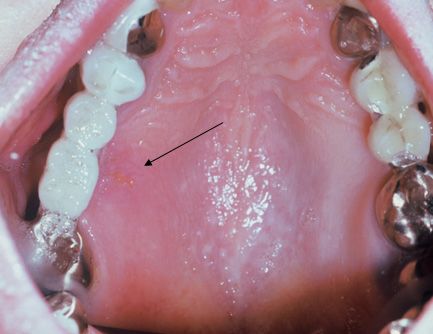

One year later the patient was re-examined when he complained of severe palatal pain adjacent to an upper bridge. This pain was preceded by an ‘itching’ sensation. Several small punctuate ulcers were observed on the lingual palate adjacent to a bridge replacing several teeth (Figure 2).